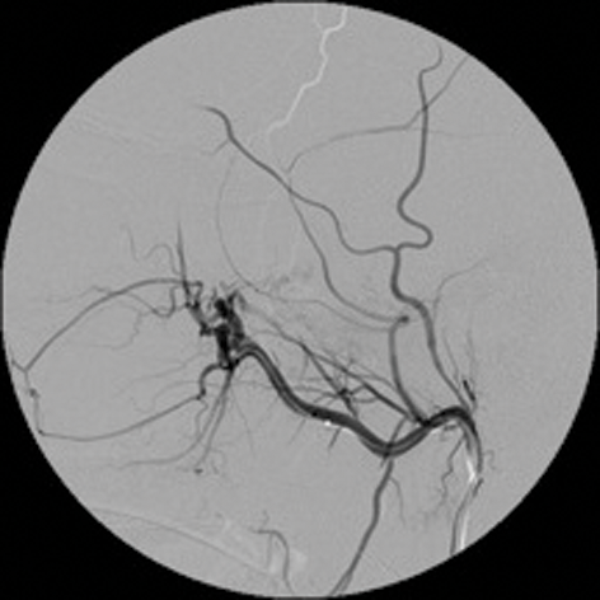

Embolisation is also effective in paragangliomas (glomus tympanicum, glomus jugulare and carotid body tumours). These are tumours arising from paraganglionic chemoreceptor cells which receive their blood supply from the ascending pharyngeal artery. They can be multicentric, locally invasive with malignant potential. Preoperative embolisation of paragangliomas greatly facilitates surgery and reduces the operative time and reduces the associated morbidity [3, 4]. (Figure 2 shows a case of preoperative embolisation of a glomus vagale tumour).

Figure 2: Glomus vagale before and after embolisation.